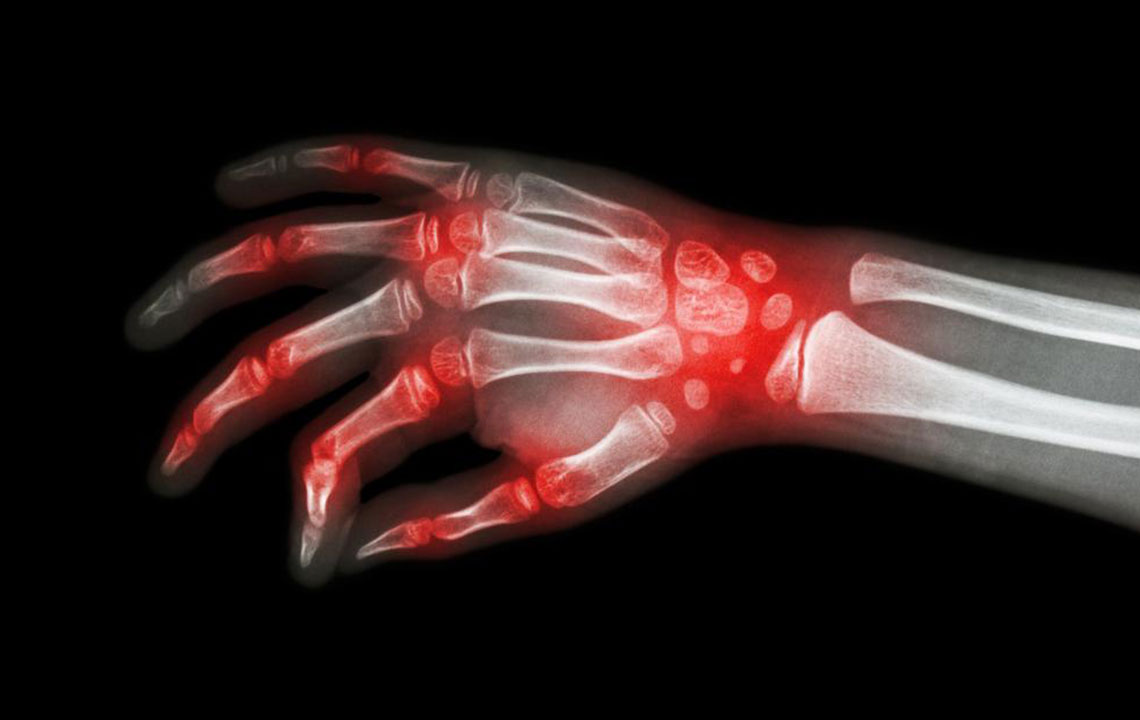

The most shared and evident similarity that rheumatoid arthritis and lupus share is joint pain. However, the levels of inflammation and swelling of joints may vary between these conditions. Joint pain is also a common symptom of patients diagnosed with either rheumatoid arthritis and lupus. Also, the joints can become warmer and tender, though this is a more prominent symptom of rheumatoid arthritis.

It is these similarities that cause a lot of confusion with the diagnosis of rheumatoid arthritis and lupus. There are several times when patients are diagnosed with rheumatoid arthritis when they actually have lupus. This usually happens in the early stages of the disorder. As the condition progresses, the difference becomes evident; rheumatoid arthritis causes bone deformity and erosion while lupus rarely leads to bone erosion.